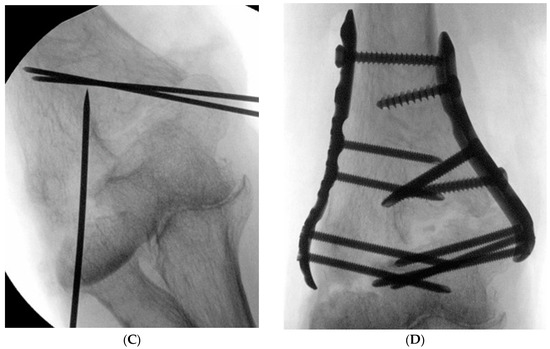

In the case of the combined mediolateral approach, as in Wei et al. [18], the medial incision was performed first and the ulnar nerve was identified but not released. A reduction clamp was used to hold the medial side of the proximal and distal fragments, and one or two Kirschner wires were used for temporary fixation. Subsequently, the lateral side of the fracture fragment was approached through a lateral incision and temporary fixation was performed in the same way, and then a 3.5 LCP distal humerus plate (DuPey Synthes, West Chester, PA, USA) was applied either orthogonally or parallelly (Figure 2A–D).

Figure 2.

Dual incision (A) medial approach, identification of ulnar nerve (arrow), temporary fixation using two Kirschner wires, (B) lateral incision, temporary fixation using one Kirschner wire, (C) intraoperative C-arm radiograph, (D) orthogonal plate fixation.